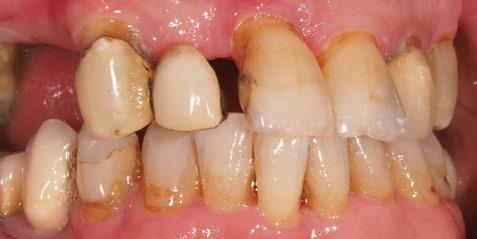

A partir del estudio radiológico y de las imágenes fotográficas podemos observar edentulismo de 17, 15, 14, 12,

Figura 1a. Foto intraoral frontal inicial.

Figura 1b. Foto intraoral lateral izquierda inicial.

Figura 1c. Foto intraoral lateral derecha inicial.

25, 26, 28, 37, 38, 47 y 48. Presentaba corona desajustada en 13 con extensión en 12, implantes en 35-36, 45-46, con coronas ferulizadas en 35-36, 45-46, y dientes anteriores superiores con enfermedad periodontal Grado IV.